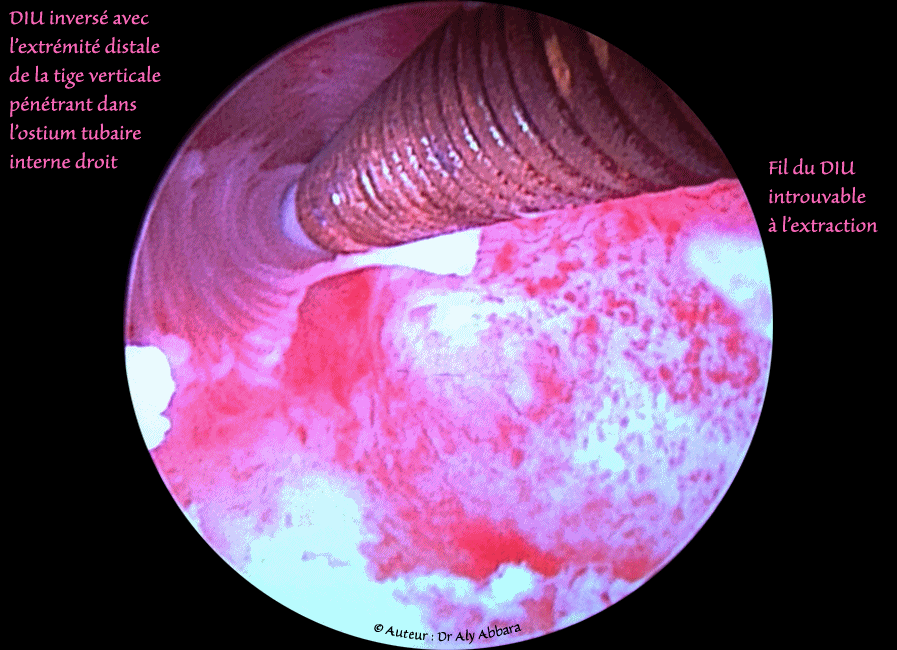

DIU inversé et pénétrant par l'extrémité distale de sa tige verticale, dans l'ostium tubaire interne droit

Un dispositif intra-utérin (DIU au cuivre, en forme de T) déplacé, inversé avec l’extrémité distale de sa tige verticale pénétrant dans l'ostium tubaire interne droit :

• Images cliniques hystéroscopiques montrant, une cavité utérine renfermant un dispositif intra-utérin (DIU) au cuivre en position anormale : inversion déplaçant l'extrémité distale de la tige verticale du DIU vers la corne droite de la cavité utérine avec pénétration de l’extrémité distale de cette tige dans l'ostium tubaire interne droit.

• Le fil du DIU n'a pas été retrouvé lors de son extraction sous contrôle hystéroscopique ; sans doute il été déjà coupé accidentellement lors des tentatives antérieures de retrait du stérilet.

• Ce DIU était à l'origine de douleur pelvienne depuis quelques mois. Une régression totale de ces douleurs a été signalée par la patiente après le retrait du DIU.